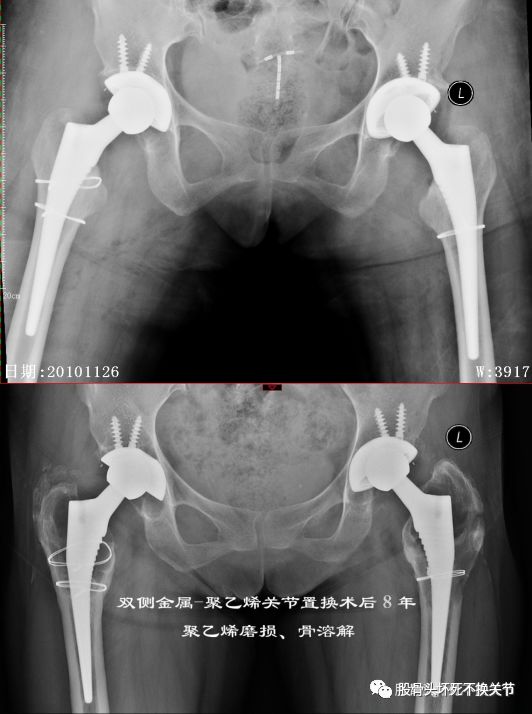

聚乙烯磨损导致骨溶解病例:

43岁,术后8年,假体磨损、骨溶解(磨损病)